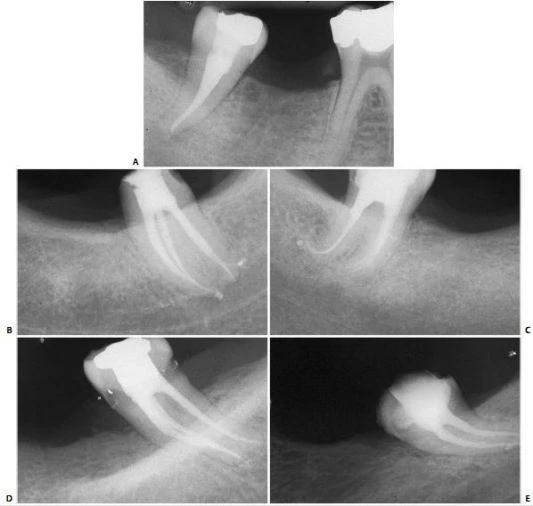

Mở xoang tủy nhìn chung răng cối lớn một hàm dưới có 2 chân phân biệt hình tròn hay thường là elip, ống tủy ở chân xa (hình 11.106) và 2 ống tủy ở chân răng gần. Trong 90% trường hợp chúng đổ ra 2 lỗ chóp khác nhau (hình 11.107) và 10% chúng hợp lại và đổ ra 1 lỗ chóp (hình 11.108).

Hình 11.106. Xoang tủy ở 1 R36: miệng củanhững ống tủy gần khá tròn còn ở ống tủy xa thì thường có hình elip.

Hình 11.107. Các ống gần của răng cối lớn một dưới có những lỗ chóp phân biệt. Chú ý rằng có nhiều ống tủy phụ ở 1/3 chóp (Courtsey of Dr. M. Scianamblo).

Hình 11.108. Các ống gần của răng cối lớn dưới hợp chung lại rồi đổ ra ở cùng một lỗ chóp. Có thể thấy nhiều ống tủy phụ ở chân xa.

–  Trong 35% trường hợp có sự hiện diện của 4 ống tủy. Chân xa có 2 ống tủy, 1 ở phía ngoài và 1 ở phía trong (hình 11.109).

Hình 11.109. A. Phim sau điều trị của  RCL 1 dưới. B. Nhìn theo chiều gần xa trên cùng răng đó có thể thấy có 2 ống tủy ở chân xa, các ống tủy chân gần mặc dù gặp nhau ở 1/3 giữa nhưng vẫn có 2 lỗ chóp. C. Xoang tủy ở R36 với 2 ống tủy ở chân gần và 2 ống tủy ở chân xa. D.Trong trường hợp răng cối lớn dưới khác cũng có 4 ống tủy, mỗi ống tủy có 1 lỗ chóp riêng.